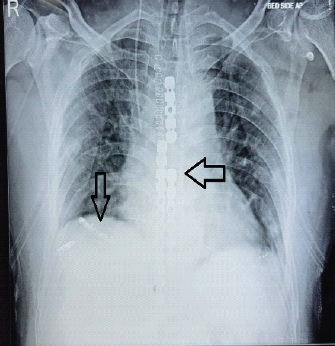

A Devastating Chest Injury: A Case Report

Bikram Keshari Kar , Sudarshan Behera , Nitin Kashyap , Rudra Narayan Dash , Rakesh Dhaka

………………………………p.107-112